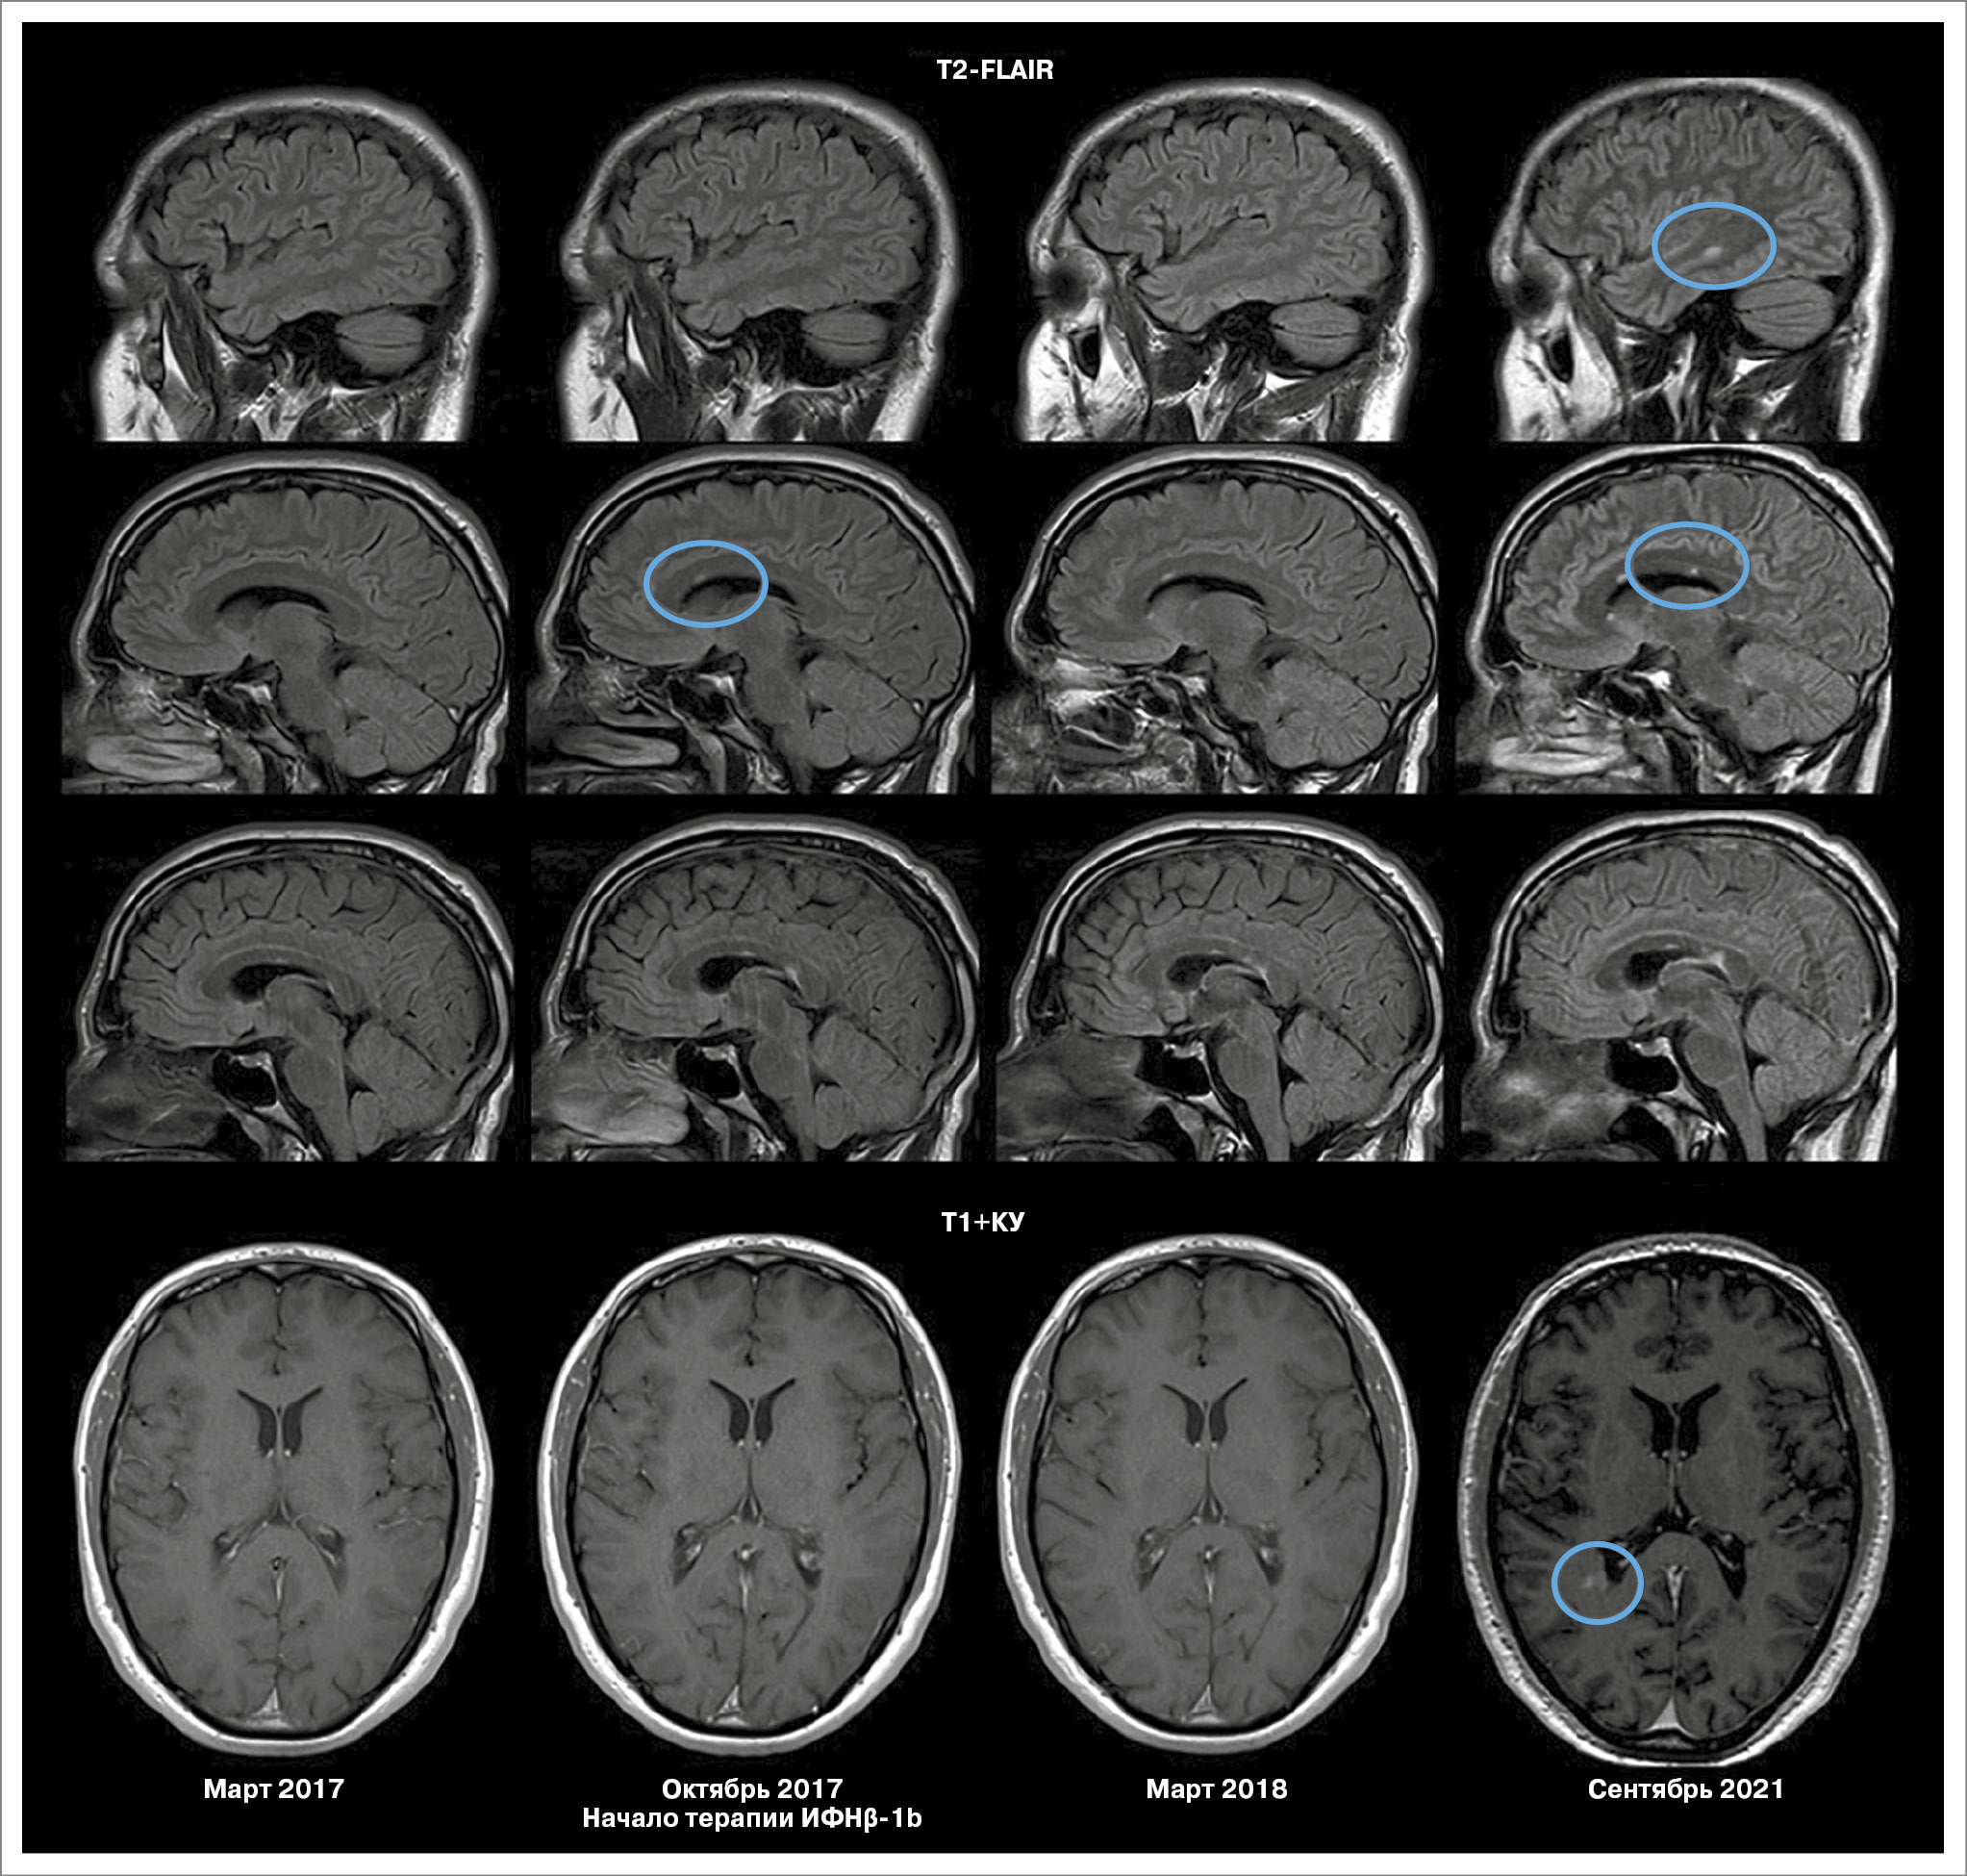

Пациентка М., женщина, 1991 г.р. Дебют заболевания в 2015 г. (возраст 24 года), когда появилось онемение в стопах, спустя несколько дней онемение распространилось полностью на ноги и нижнюю часть живота. По данным МРТ головного мозга: множественные очаги в белом веществе головного мозга (перивентрикулярные, юкстакортикальные, в том числе с накоплением контрастного вещества одним очагом), в левой половине моста (рис. 3), а также в грудном отделе спинного мозга на уровне ThV–ThVI.

Рис. 3. МРТ пациентки М. на фоне терапии ИФНβ-1b с 2015 г. (клинический случай 3).

Выполнено исследование сыворотки и ликвора на олигоклональные антитела, тип синтеза 2. Поставлен диагноз «РС, ремиттирующее течение».

Проведена пульс-терапия метилпреднизолоном в курсовой дозе 3 г с положительным эффектом, зарегистрировано снижение балла EDSS до 2,0. Назначен ПИТРС ИФНβ-1b (Инфибета®, АО «Генериум») 9,6 млн МЕ подкожно через день. На фоне лечения (8 лет терапии) клинических обострений не зарегистрировано. Отмечалась активность по данным МРТ в виде появления новых очагов перивентрикулярно в течение первых 6 мес от начала терапии. В 2023 г. на фоне терапии наступила беременность, протекала без осложнений, завершена естественными родами без осложнений. После родоразрешения пациентка продолжила прием препарата. В 2024 г. появились перивентрикулярные очаги, один из которых накапливал контрастное вещество (см. рис. 3). В настоящее время пациенткой принято решение также продолжать лечение ИФНβ-1b. EDSS остается стабильным – 1,5 балла.